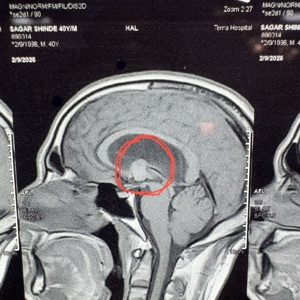

Brain tumor surgery can be performed using open surgery or minimally invasive endoscopic approaches. Open surgery involves craniotomy, where part of the skull is removed to access the tumor. Endoscopic approaches use small incisions and a camera to remove or biopsy the tumor, resulting in quicker recovery times. The choice depends on the tumor's size, location, and type.

Minimally invasive brain surgery involves the use of small incisions and advanced instruments, like endoscopes, to perform procedures with less damage to surrounding tissues. It's used for certain brain tumors, hydrocephalus, and other conditions located in difficult-to-reach areas. Benefits include reduced scarring, faster recovery, and less postoperative pain compared to traditional surgery.

Surgical management of traumatic brain injuries (TBI) focuses on pressure relief, bleeding control, and repair of fractures. Strategies may include craniotomies to remove hematomas or relieve intracranial pressure, debridement of damaged tissue, and stabilization of skull fractures. The surgery aims to prevent further brain injury and address life-threatening conditions, with rehabilitation often following.